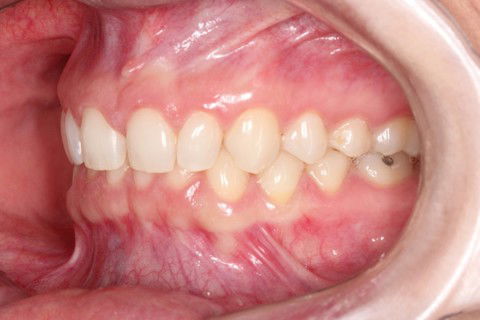

Inicial

Paciente do sexo feminino, 29 anos.

Queixa principal: Espaços generalizados entre os dentes superiores (Diastemas), na qual a paciente relatava apresentar uma aparência infantil. Foi diagnosticado dentes com discrepância negativa de forma e tamanho, mas bem posicionados na arcada. Não sendo indicado fechamento de espaço através aparatologia ortodôntica.